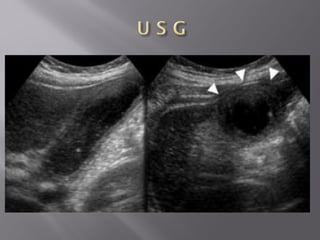

Normal Appendix  Atsonography and CT the appendix is seen as a blind-ending nonperistaltic tubular structure arising from the base of the cecum.  Do not mistake a small bowel loop for the appendix.  The outer-to-outer diameter of the appendix is the most important imaging criterion.

Long Axis ShortAxis TARGET SIGN

 Diameter largerthan 6 mm  Usually surrounded by inflamed fat  Presence of a fecolith  Hypervascularity on power Doppler